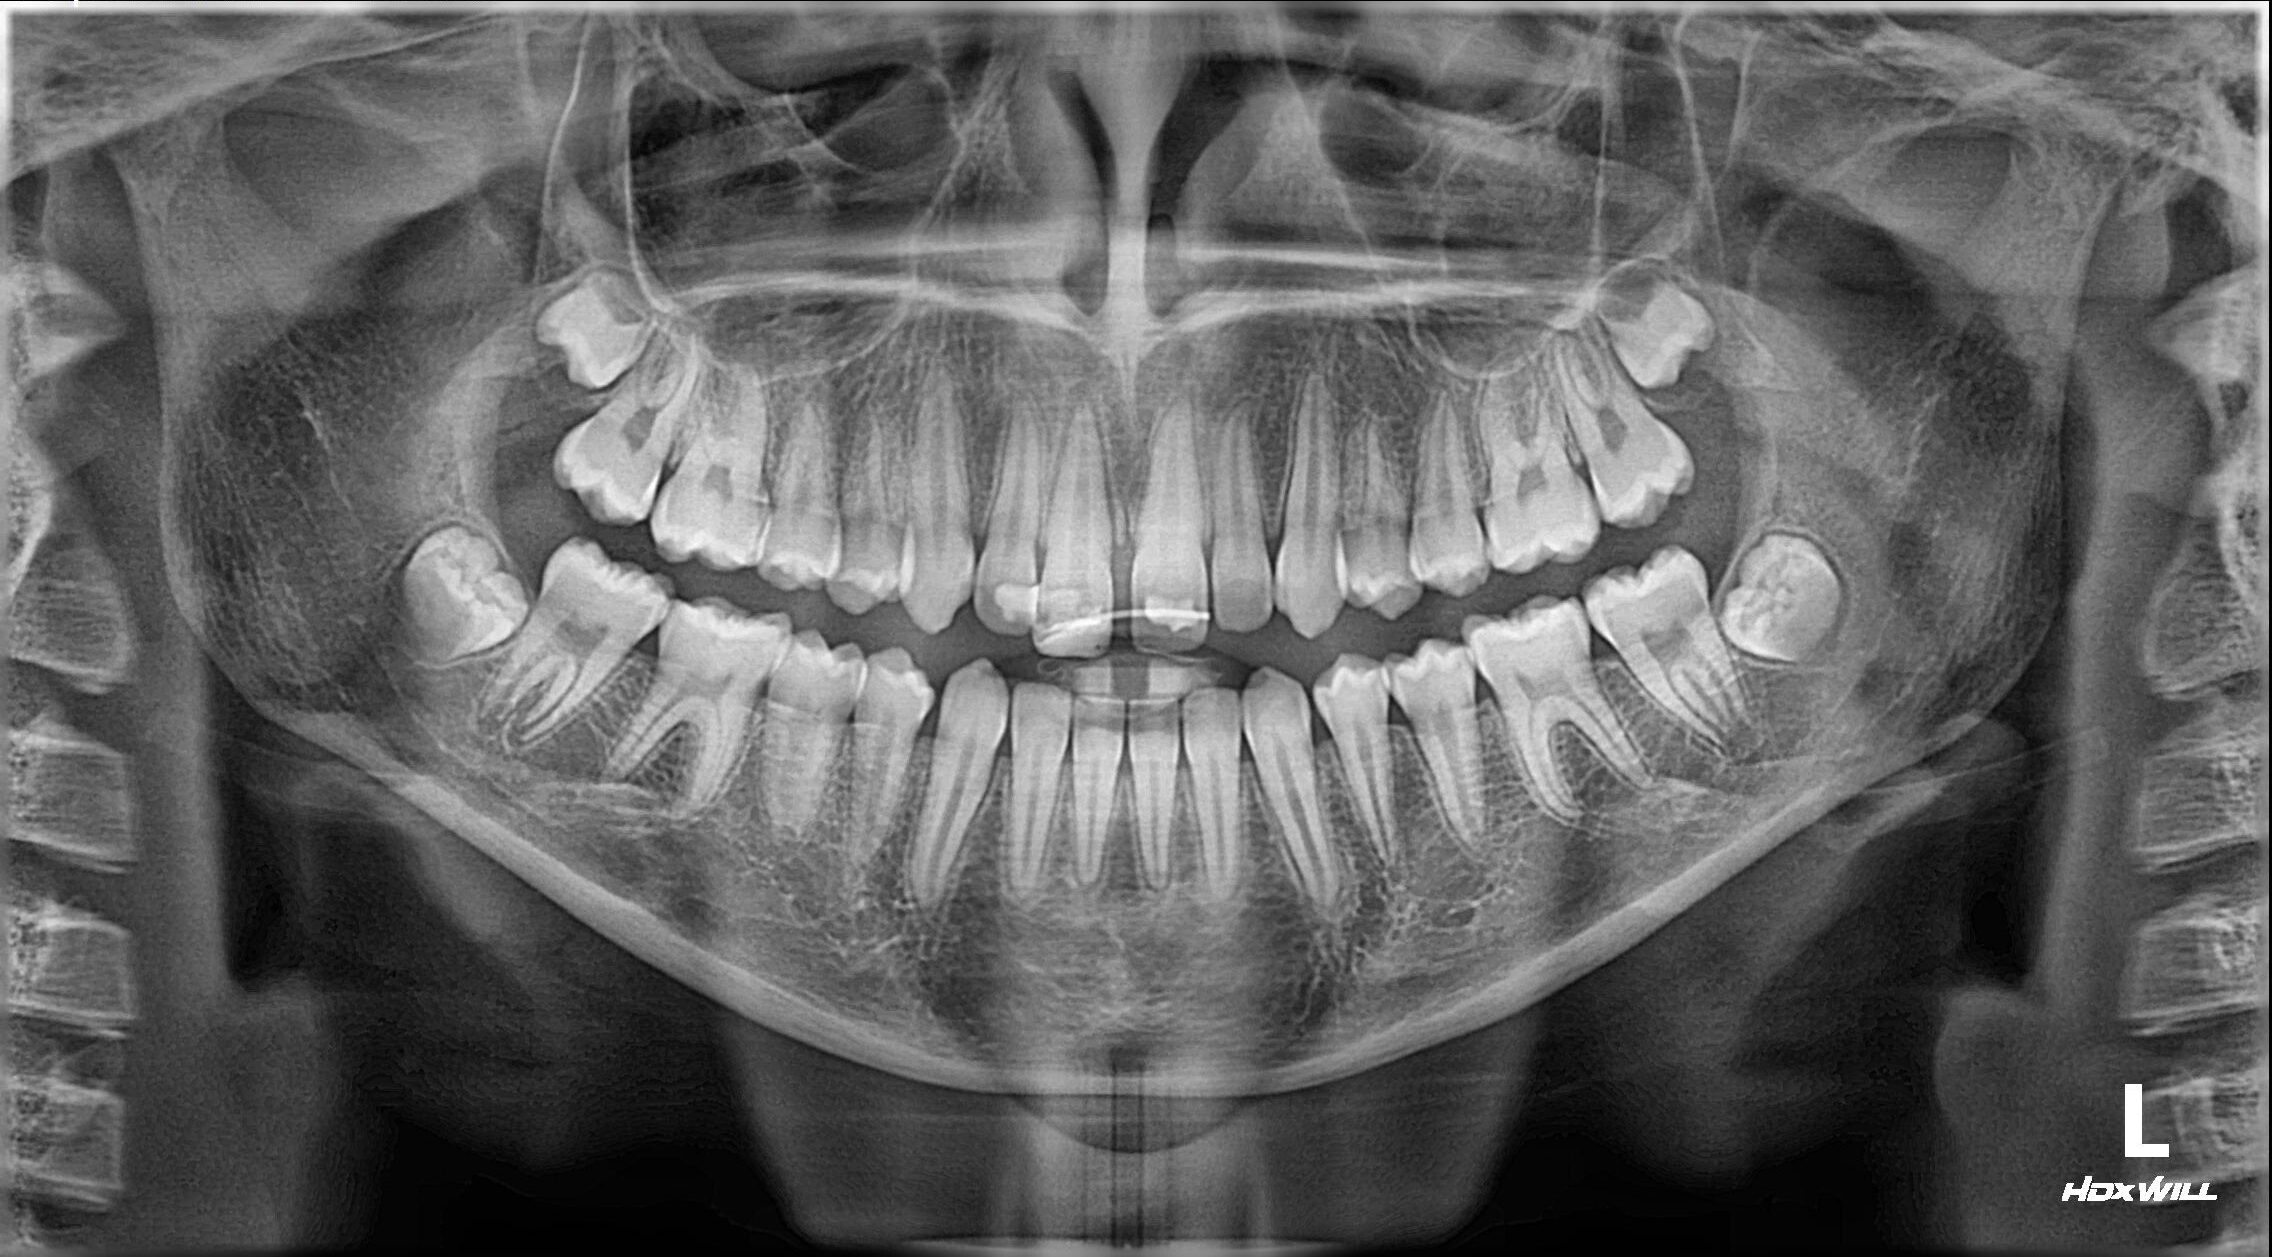

4. Radiografi para dhe pas ndërhyrjes

Radiografitë lejuan vlerësimin e:

• pozicionimit të saktë të dhëmbit të reimplantuar,

• gjendjes së rrënjës dhe alveolës,

• dëmtimeve të mundshme të strukturave mbështetëse,

• dokumentimit të gjendjes fillestare për monitorim afatgjatë.